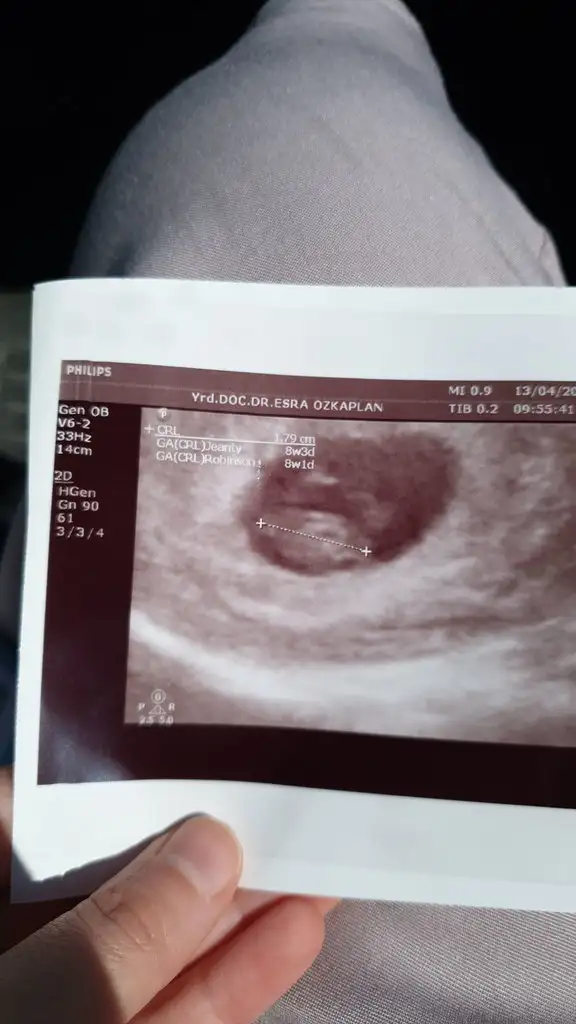

Selam kızlar bugün doktora gittim kalp atışı için.hersey yolunda şükür. Ben 7+6 diyordum da 8+3 imiş ultrason görüntüsünü atayım kızlar size bi bakın. Cinsiyet tahmini edenler oluyordu burada bebeğin konumuna göre:) tabi hepsi ihtimal ama olsun merak ediyorum

• IMG-20190413-WA0002.webp

27,7 KB · Görüntüleme: 76

Ramzi teorosine sanki erkek gibi sağlıkla gelsin tabi öncelikle de